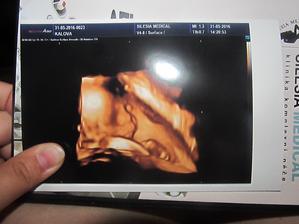

Klokan přiletí v září

jééé, krásný bobišek 😉 a už takový velký...